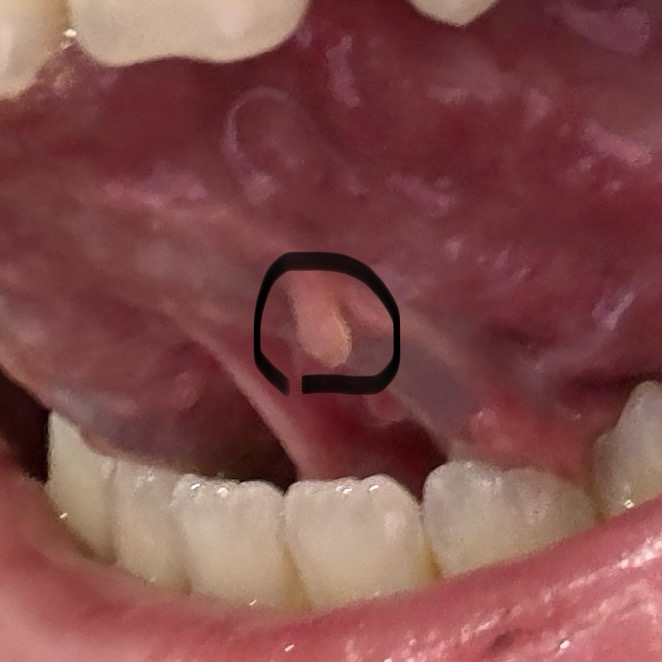

혀 밑에 돌기처럼 이상한 살이 있어요

검은색 동그라미 부분이

누워서 혀에 붙어 있다가

저렇게 떠있다가 합니다.

제거 수술이 필요한건가요?

암같은 악성 종양 일까요??

• 안녕하세요. 신성현 의사입니다.

악성으로 보이지는 않으며 인후두부에 생길수 있는 양성 용종 정도로 보입니다. 이비인후과 진료를 보시고 추적관찰을 해보시기 바랍니다.